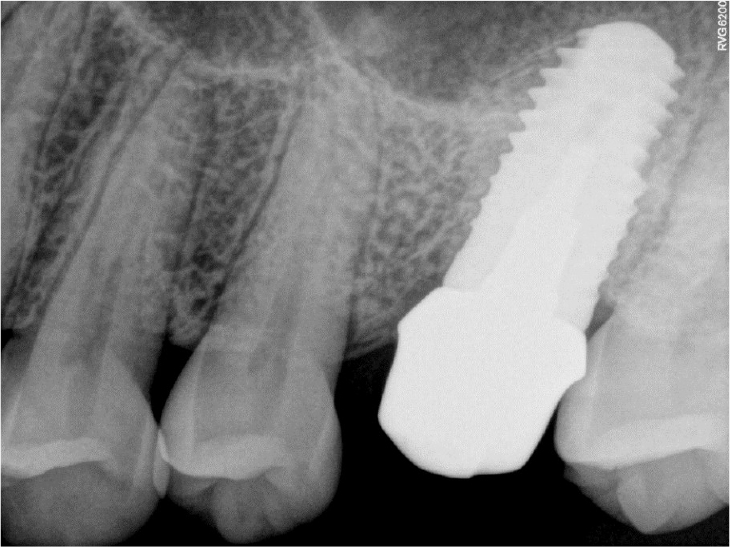

Subsequently, to prepare a space for the post, the inner surface of the fixture was prepared using a metal cutting bur (FG H34-012; Komet Dental, Lemgo, Germany) and a fine-grit round end taper diamond bur (TR 26F, 1.8 mm; Mani, Tochigi, Japan) in a high-speed handpiece (320,000 rpm) under water-cooling. In addition, a groove was formed on the fixture platform using a diamond bur to prevent horizontal rotation when connecting the post (Fig. 3).

The impression was taken with the indirect method of using a plastic impression post (Parapost® Green No. 7, 1.75 mm; Coltene/Whaledent, Altstatten, Switzerland) (Fig. 4) and polyvinylsiloxane (PVS) materials. The diameter of the impression post was similar to that of the bur used to prepare the inner surface of the fixture. In addition, an adhesive (V.P.S. tray adhesive; Kerr dental, Brea, CA, USA) was applied around the impression post to increase adhesion with the impression material.

The double mixing method using a metal tray was selected, with heavy- and light-viscosity impression materials (Imprint II Garant; 3M ESPE, Maplewood, MN, USA). After taking impressions, the inside of the fixture was temporarily restored with a temporary restoration material (Selection S-temp flow; Shinhung, Seoul, Korea) to the upper gingival margin. A temporary filling material was used instead of a healing abutment to prevent soft tissue overgrowth around the implant platform.